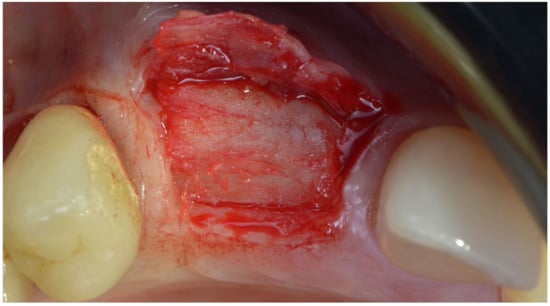

The bone lamina was shaped as a saddle, fixed to the buccal bone with two pins, and then, after the area was grafted with a mix of autogenous bone and collagenated xenograft (50–50%), reflected and stabilized under the palatal flap (Figure 7). Flaps were secured with 4.0 resorbable sutures and healing was uneventful.

Figure 7.

Bone lamina in place, arrows indicate the thickness of the lamina (1 mm) inducing both GBR and GTR effect.